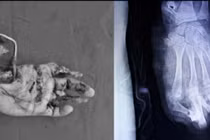

Bệnh viện Nhi đồng 2 vừa tiếp nhận một trường hợp bệnh nhi 13 tuổi bị chấn thương nặng vùng mặt và mắt do pháo nổ. Theo lời gia đình, pháo được đặt mua trên mạng và đốt tại nhà.

Hậu quả để lại vô cùng nghiêm trọng: Bỏng nặng vùng mặt gây nhiều mảng hoại tử da; Tổn thương mắt nghiêm trọng, bao gồm rách giác mạc, xuất huyết tiền phòng; Nguy cơ mất thị lực vĩnh viễn.

Trẻ bỏng nặng do pháo nổ - Ảnh BVCC

Bệnh viện Nhi đồng 2 mới đây đã tiếp nhận một bệnh nhi 13 tuổi ở Đồng Nai bị bỏng nặng vùng đầu mặt sau khi đốt pháo mua trên mạng xã hội. Do đứng quá gần thời điểm pháo phát nổ, luồng nhiệt và áp lực mạnh đã gây tổn thương nghiêm trọng, buộc các bác sĩ phải điều trị tích cực cho bệnh nhân trong thời gian dài.